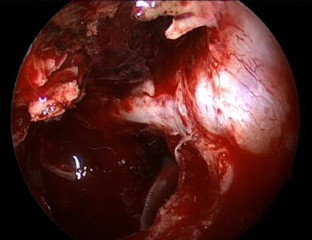

Fig. 3